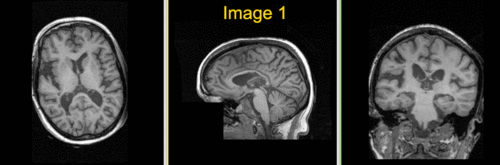

Slicer Registration Library Case #16: Manual alignment of intra-subject Brain MRI

| fixed image/target | moving image |

- fixed: 1mm isotropic;256 x 256 x 146

- moving: 1.2mm isotropic; 256 x 256 x 116